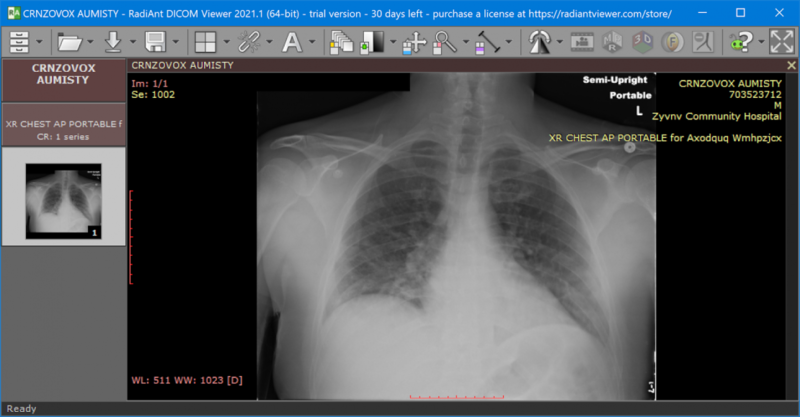

C. Medical Image Formats¶

Medical imaging uses specialized formats beyond standard JPEGs and PNGs:

- DICOM (Digital Imaging and Communications in Medicine)

- Standard format for medical imaging

- Contains both pixel data AND metadata

- Metadata includes:

- Patient information (ID, name, demographics)

- Acquisition parameters (modality, date, equipment settings)

- Organizational hierarchy (study, series, instance)

- Loading images in DICOM and standard formats using Pydicom, Pillow, and OpenCV

- Inspecting image properties and metadata

- Preprocessing: resizing, normalization, color space conversion

- Visualization with Matplotlib